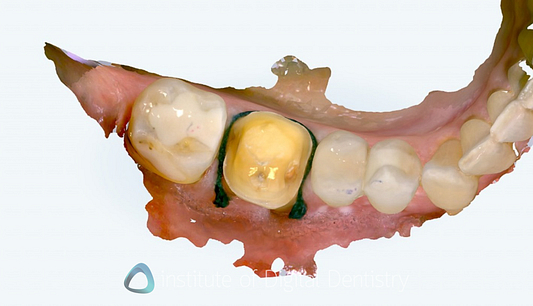

Beyond dimensional accuracy, my favorite part of the Lumina is the scan textures and quality. It produces exceptional final scans. These are the nicest I have seen on the market.

The photorealistic textures are simply unmatched by any other scanner currently available in terms of detail, resolution, and colors. These visuals offer both clinical and communication advantages, and they work well within the extensive range of patient communication apps available within the Align Oral Health Suite.

These scan images really are nice to look at, even for patients. I mean, the detail capture is market-leading, with the scanning picking up even the twists on a ligature tie (see the images below). Gingival texture, tooth characteristics, and restoration details appear with clarity that approaches the quality of intraoral photography. It really is incredible tech.